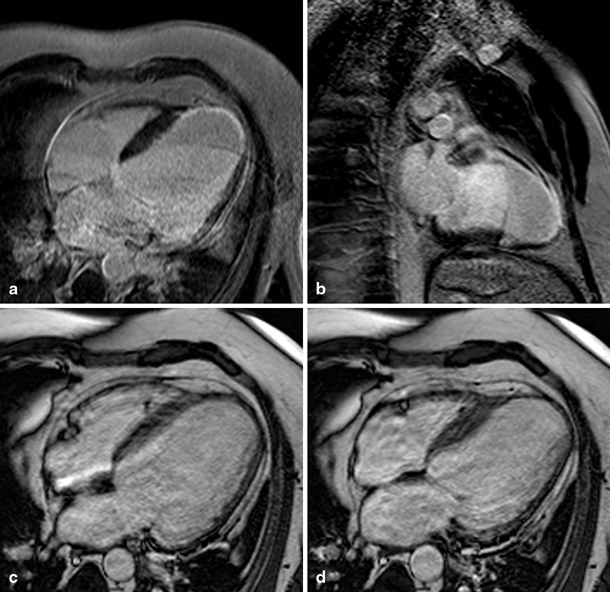

A total of 21 patients with IHD had infarcts in the LAD territory and 2 patients in the LAD and LCX territory (Fig. 1). Infarction of the RV free wall was recognised in only one patient of the IHD group: a small area of late enhancement of the RV apex was visible on CMR images. This patient had a transmural infarction in the LAD territory showing late enhancement from the anterior wall to the apex of the LV continuing to the RV apex (Fig. 2). None of the patients with DCM had focal fibrosis of the RV free wall myocardium on CMR late enhancement images.

Fig. 2

Late gadolinium enhancement (four-chamber view (a), 2 chamber view (b)) and cine (four-chamber view in end-diastole (c) and end-systole (d)) magnetic resonance images of a patient with a large myocardial infarction (left ventricular ejection fraction 22 %) of the left anterior descending coronary artery, continuing from the left ventricular apex to the right ventricle (right ventricular ejection fraction 57 %) (white arrow) A corresponding akinetic region of the right ventricular apex can be depicted on the end-systolic cine image (D, black arrow)